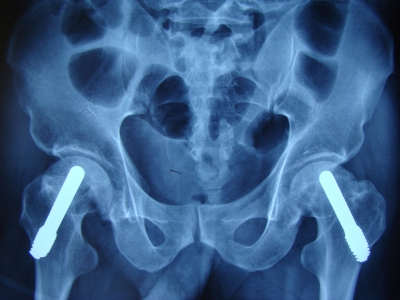

其适应症有:原发性髋关节骨性关节炎,创伤性髋关节骨性关节炎,类风湿性髋关节炎,perthes 病,股骨头坏死,股骨头骺滑脱症。该项技术适应症必须严格控制,对于骨质疏松症,髋关节发育不良,股骨颈畸形和有过敏体质的患者需慎重选择。(图6)

(图6)双侧短柄关节置换术一例